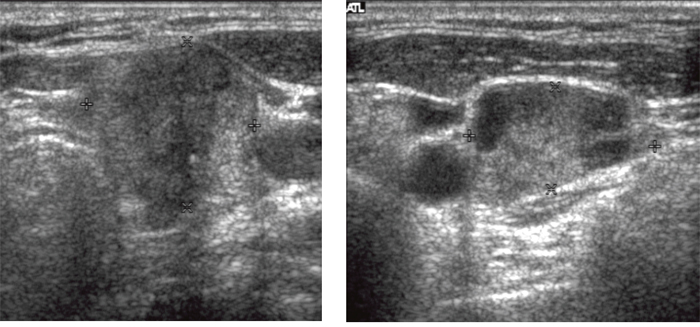

Figure 2: A 52-year-old woman with a papillary thyroid carcinoma with BRAF mutation in right thyroid lobe. Transverse (A) and longitudinal (B) ultrasonographic images show a 2.2-cm solid mass with spiculated margin, irregular shape, hypoechogenicity, non-parallel orientation, and micro- and macrocalcifications. This mass was classified as K-TIRADS category 5. After surgery, central lymph nodes were confirmed as metastases and TNM stage was classified as III. There was no recurrence during 11.4 years of follow-up.

Figure 3: A 56-year-old woman with a papillary thyroid carcinoma with TERT+BRAF mutations in left thyroid lobe. Transverse (A) ultrasonographic image shows a 3.0-cm solid mass with spiculated margin, irregular shape, hypoechogenicity, non-parallel orientation, and microcalcifications. Transverse (B) ultrasonographic image shows an enlarged lymph node with increased cortical echogenicity and cystic changes in left level IV. The main mass was classified as K-TIRADS category 5 and the level IV lymph node was considered metastatic. After surgery, level IV lymph nodes were confirmed as metastases and TNM stage was classified as IV. Bilateral lung metastases and operative bed recurrences were diagnosed 4.4 years after surgery.